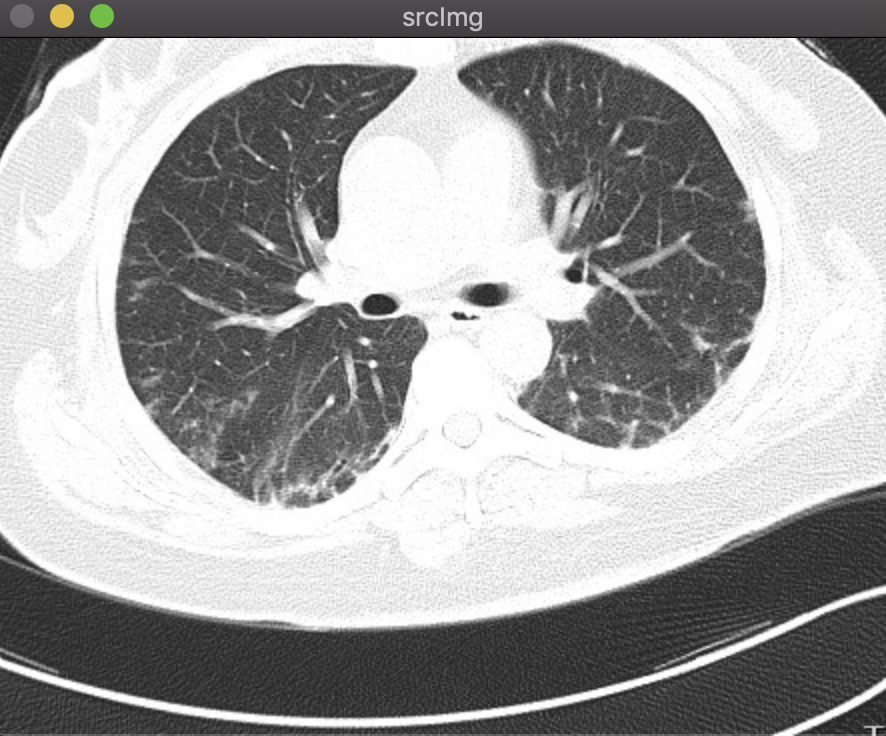

结果:

以下为原图,先转化为灰度图,再转换为二值图。

鼠标先在二值图左肺选取一个种子点,按‘b‘进行分割;然后在二值图右肺选取一个种子点,按‘b‘进行分割,之后做或运算,将两个分割结果合并;最后与灰度图做与运算得到最终分割结果。